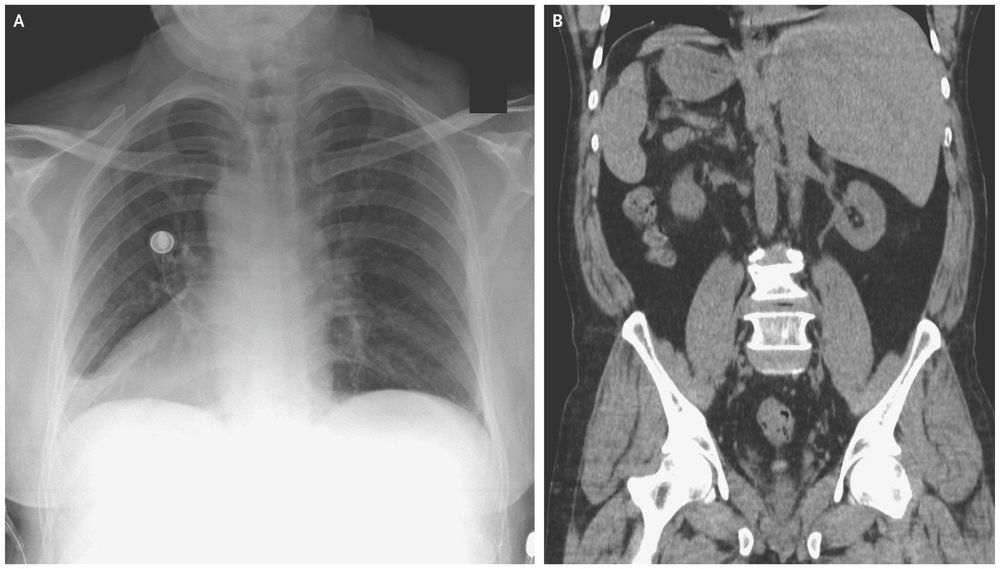

(हृदय उजव्या बाजूला)

जमालुद्दीन नावाचा हा माणूस नुकतंच पोटदुखीमुळे डॉक्टरांकडे आला होता. डॉक्टरांनी एक्स-रे काढल्यावर त्यांना धक्काच बसला. जमालुद्दीनच्या शरीरातील अवयव विरुद्ध बाजूला होते. त्याचं हृदय उजवीकडे आहे तर यकृत आणि पित्ताशय डाव्या बाजूला आहेत.

त्याच्या पोटात दुखण्याचं कारण होतं पित्ताशयात असलेले खडे, पण पित्ताशय डाव्या बाजूला असल्याने ऑपरेशन करणं अवघड झालं आहे. यासाठी आता नवीन तंत्रज्ञान वापरून त्याच्यावर उपचार केले जातील.

मंडळी, या प्रकाराला शास्त्रीय भाषेत Situs inversus म्हणतात. ही एक अवस्था असून यात माणसाच्या शरीरातील प्रमुख अवयव उलट्या दिशेत असतात. एकूण लोकसंख्येच्या अवघ्या ०.०१% एवढ्याच लोकांमध्ये ही अवस्था सापडते. बऱ्याचशा लोकांना आपल्या शरीरात असे उलटे अवयव आहेत हे माहितीच नसतं. त्याचा शरीरावर विपरीत परिणाम देखील होत नसतो.